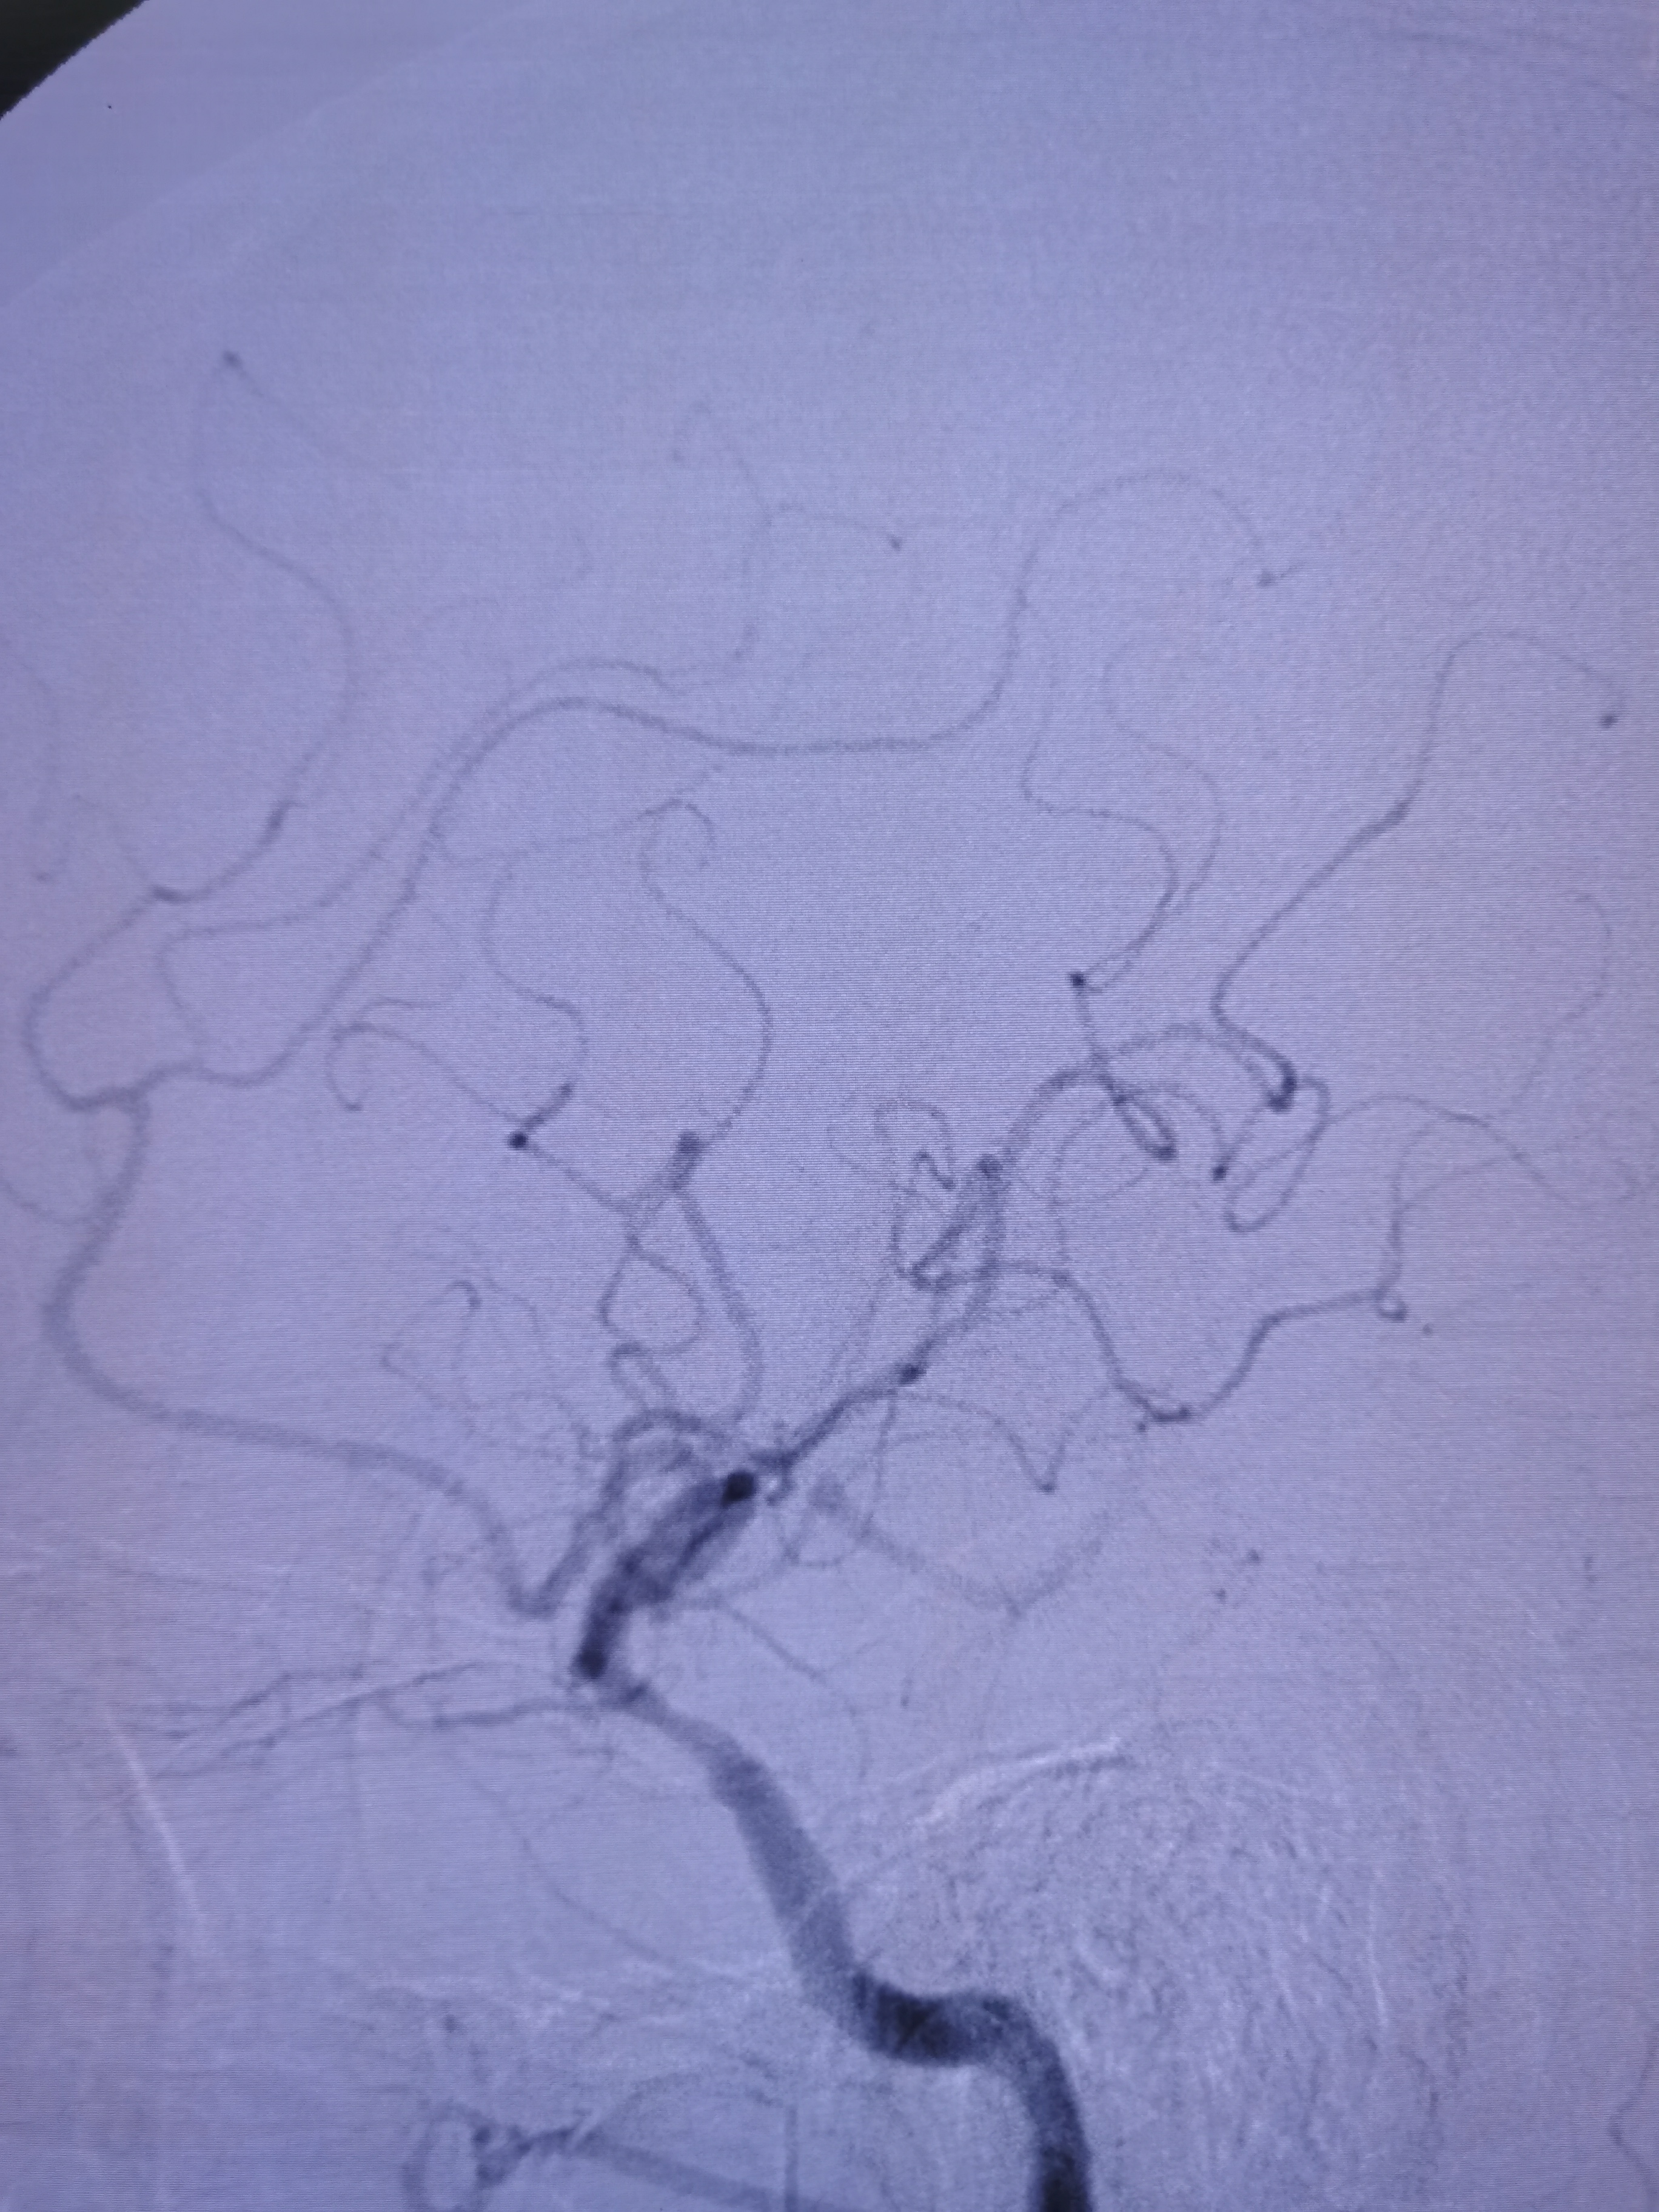

DSA示右椎动脉优势,起始部极重度狭窄,左侧椎动脉完全反向血流,动脉晚期可见左侧锁骨下动脉闭塞端。

右椎动脉起始部极重度狭窄。

右颈颅内段动脉硬化,右侧后交通动脉开放。